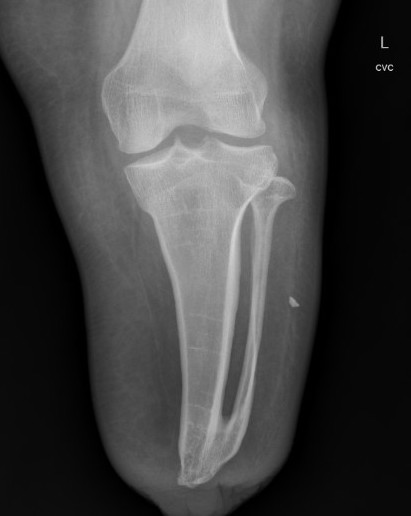

Boyd / Pirogoff amputation

Concept

- Boyd: talectomy and calcaneotibial arthrodesis

- Pirogoff: talectomy and calcaneotibial arthrodesis with partial calcaneal resection

- forward translation of the calcaneus

- fixation to obtain fusion

Technique

- dorsal incision from tip lateral malleolus to medial malleolus

- planter incision transversely across sole at level metatarsal bases

- amputate forefoot through Chopart joint

- excise talus

- anterior calcaneal osteotomy transversely across calcaneum at level of peroneal tubercle

- shift calcaneum anteriorly

- excise cartilage of distal tibia / fibula & superior calcaneum

- calcaneo / tibial arthrodesis

Issues

- prolonged non weight bearing periods to obtain fusion

- small surface area / risk of ulcers

- risk of nonunion of arthrodesis

- LLD of 2 - 4 cm

- need custom AFO to ambulate